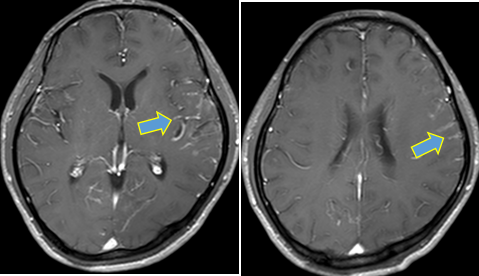

颅脑强化MR:双侧大脑半球及小脑脑膜走行区见线条状及结节状强化,以左颞顶部为著。符合脑膜转移MR表现。

图片YkT帝国网站管理系统

颅脑强化MRI提示:口服阿美替尼2个月后,双侧大脑半球及小脑脑膜走行区见线条状及结节状强化,较前期局部好转;8月26日末次随访时脑室系统大小及形态未见异常。YkT帝国网站管理系统